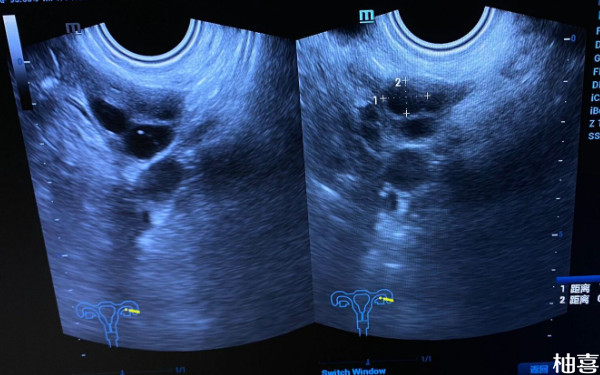

青岛市立医院试管内膜检查月经第四天可以做吗?

在青岛市立医院做试管期间,如果患者要检查内膜的话,那么可以在月经第四天到医院就诊。一般来说,月经第四天的时候,子宫内膜会比较薄,方便医生判断卵巢功能以及排卵情况。另外,此时还可以检测性激素六项水平,为胚胎移植手术做好相关准备。需注意,每个人的卵巢、月经、内膜等情况都是不同的,这里建议患者听从医生安排即可。